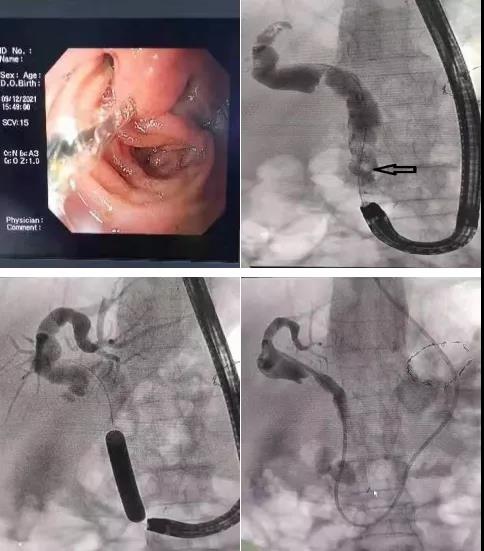

近日,消化內(nèi)二科成功開展首例畢Ⅱ式胃大部切除術(shù)后復發(fā)難治性膽總管結(jié)石的ERCP取石手術(shù)。

患者81歲高齡女性,既往胃大部切除畢Ⅱ式吻合術(shù)后30余年,因發(fā)熱、腹痛入院,診斷為膽總管結(jié)石、急性梗阻性化膿性膽管炎?;颊叽嬖诟啐g、感染性休克等情況,病情復雜危重,蓋偉主任立即爭分奪秒組織科內(nèi)專家仔細分析討論病情,決定首選ERCP取石術(shù)。

與家屬充分溝通后,蓋偉主任和田宗彪主治醫(yī)師開始內(nèi)鏡下取石術(shù),交替使用十二指腸鏡和胃鏡找到改道后的十二指腸乳頭,通過胃鏡完成插管、乳頭擴張成型、取石及鼻膽管置入,順利完成手術(shù)。術(shù)后,患者腹痛、發(fā)熱、黃疸等癥狀消失,三天后順利出院。